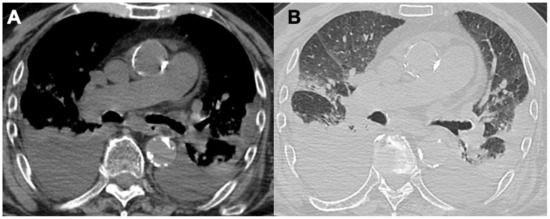

| MPA | Bronchiectasis (40%) | GGO (23–94%); reticular changes (UIP, NSIP, and DIP patterns); consolidations; diffuse alveolar hemorrhage (25–60%) | Pleural effusion; pleuritis | |